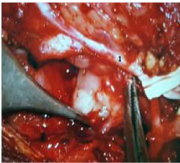

A total parotidectomy with preauricular skin incision was planned. However, intra-operatively involvement of surrounding muscles, periparotid lymph nodes and level II b / III lymph nodes was noted. Facial nerve and its terminal branches were preserved with careful dissection, however there was adherence of inferior division of facial nerve to the tumour mass which was cleared carefully under microscopic control. The retromandibular vein was ligated and a globular mass seen arising from the deep lobe of the parotid. The tumour was removed in to along with other smaller mass from the deep lobe. Total parotidectomy was performed along with excision of unhealthy overlying skin, part of upper and anterior border of Sternocleidomastoid muscle and a part of posterior belly of Digastric muscle. Level II b and III lymph node clearance was done. A suction drain was put for 48hours. Post operative recovery was uneventful with minimal deviation of angle of the mouth which recovered fully after two weeks. Histopathology of the mass revealed diffuse large B cell NHL showing sheets and strands of atypical lymphoid cells with involvement of superficial, deep lobe of parotid, Sternocleidomastoid muscle and Digastric muscle. Skin and level IIb and III lymph nodes also revealed similar population of atypical cells with perinodal extension. The tumour cells were positive strongly for CD20, LCA and CD79a on Immunohistochemistry (IHC). However, the cells were negative for CD5, CD3, EMA, CK and TdT on IHC. The Ki-67 labelling index was 100% (Figures 3-8).

Figure 3 Facial Nerve was identified and secured with careful dissection. Deep lobe tumour can be seen inferior to the lower division of facial nerve (arrow).

Figure 4 Intraoperative image showing: Deep lobe tumor of parotid being delivered1, sternomastoid muscle2, facial nerve3 and Spinal accessory nerve4.

Figure 5 Under microscopic control the adherent lower division of facial nerve1 was freed from the deep lobe tumour.